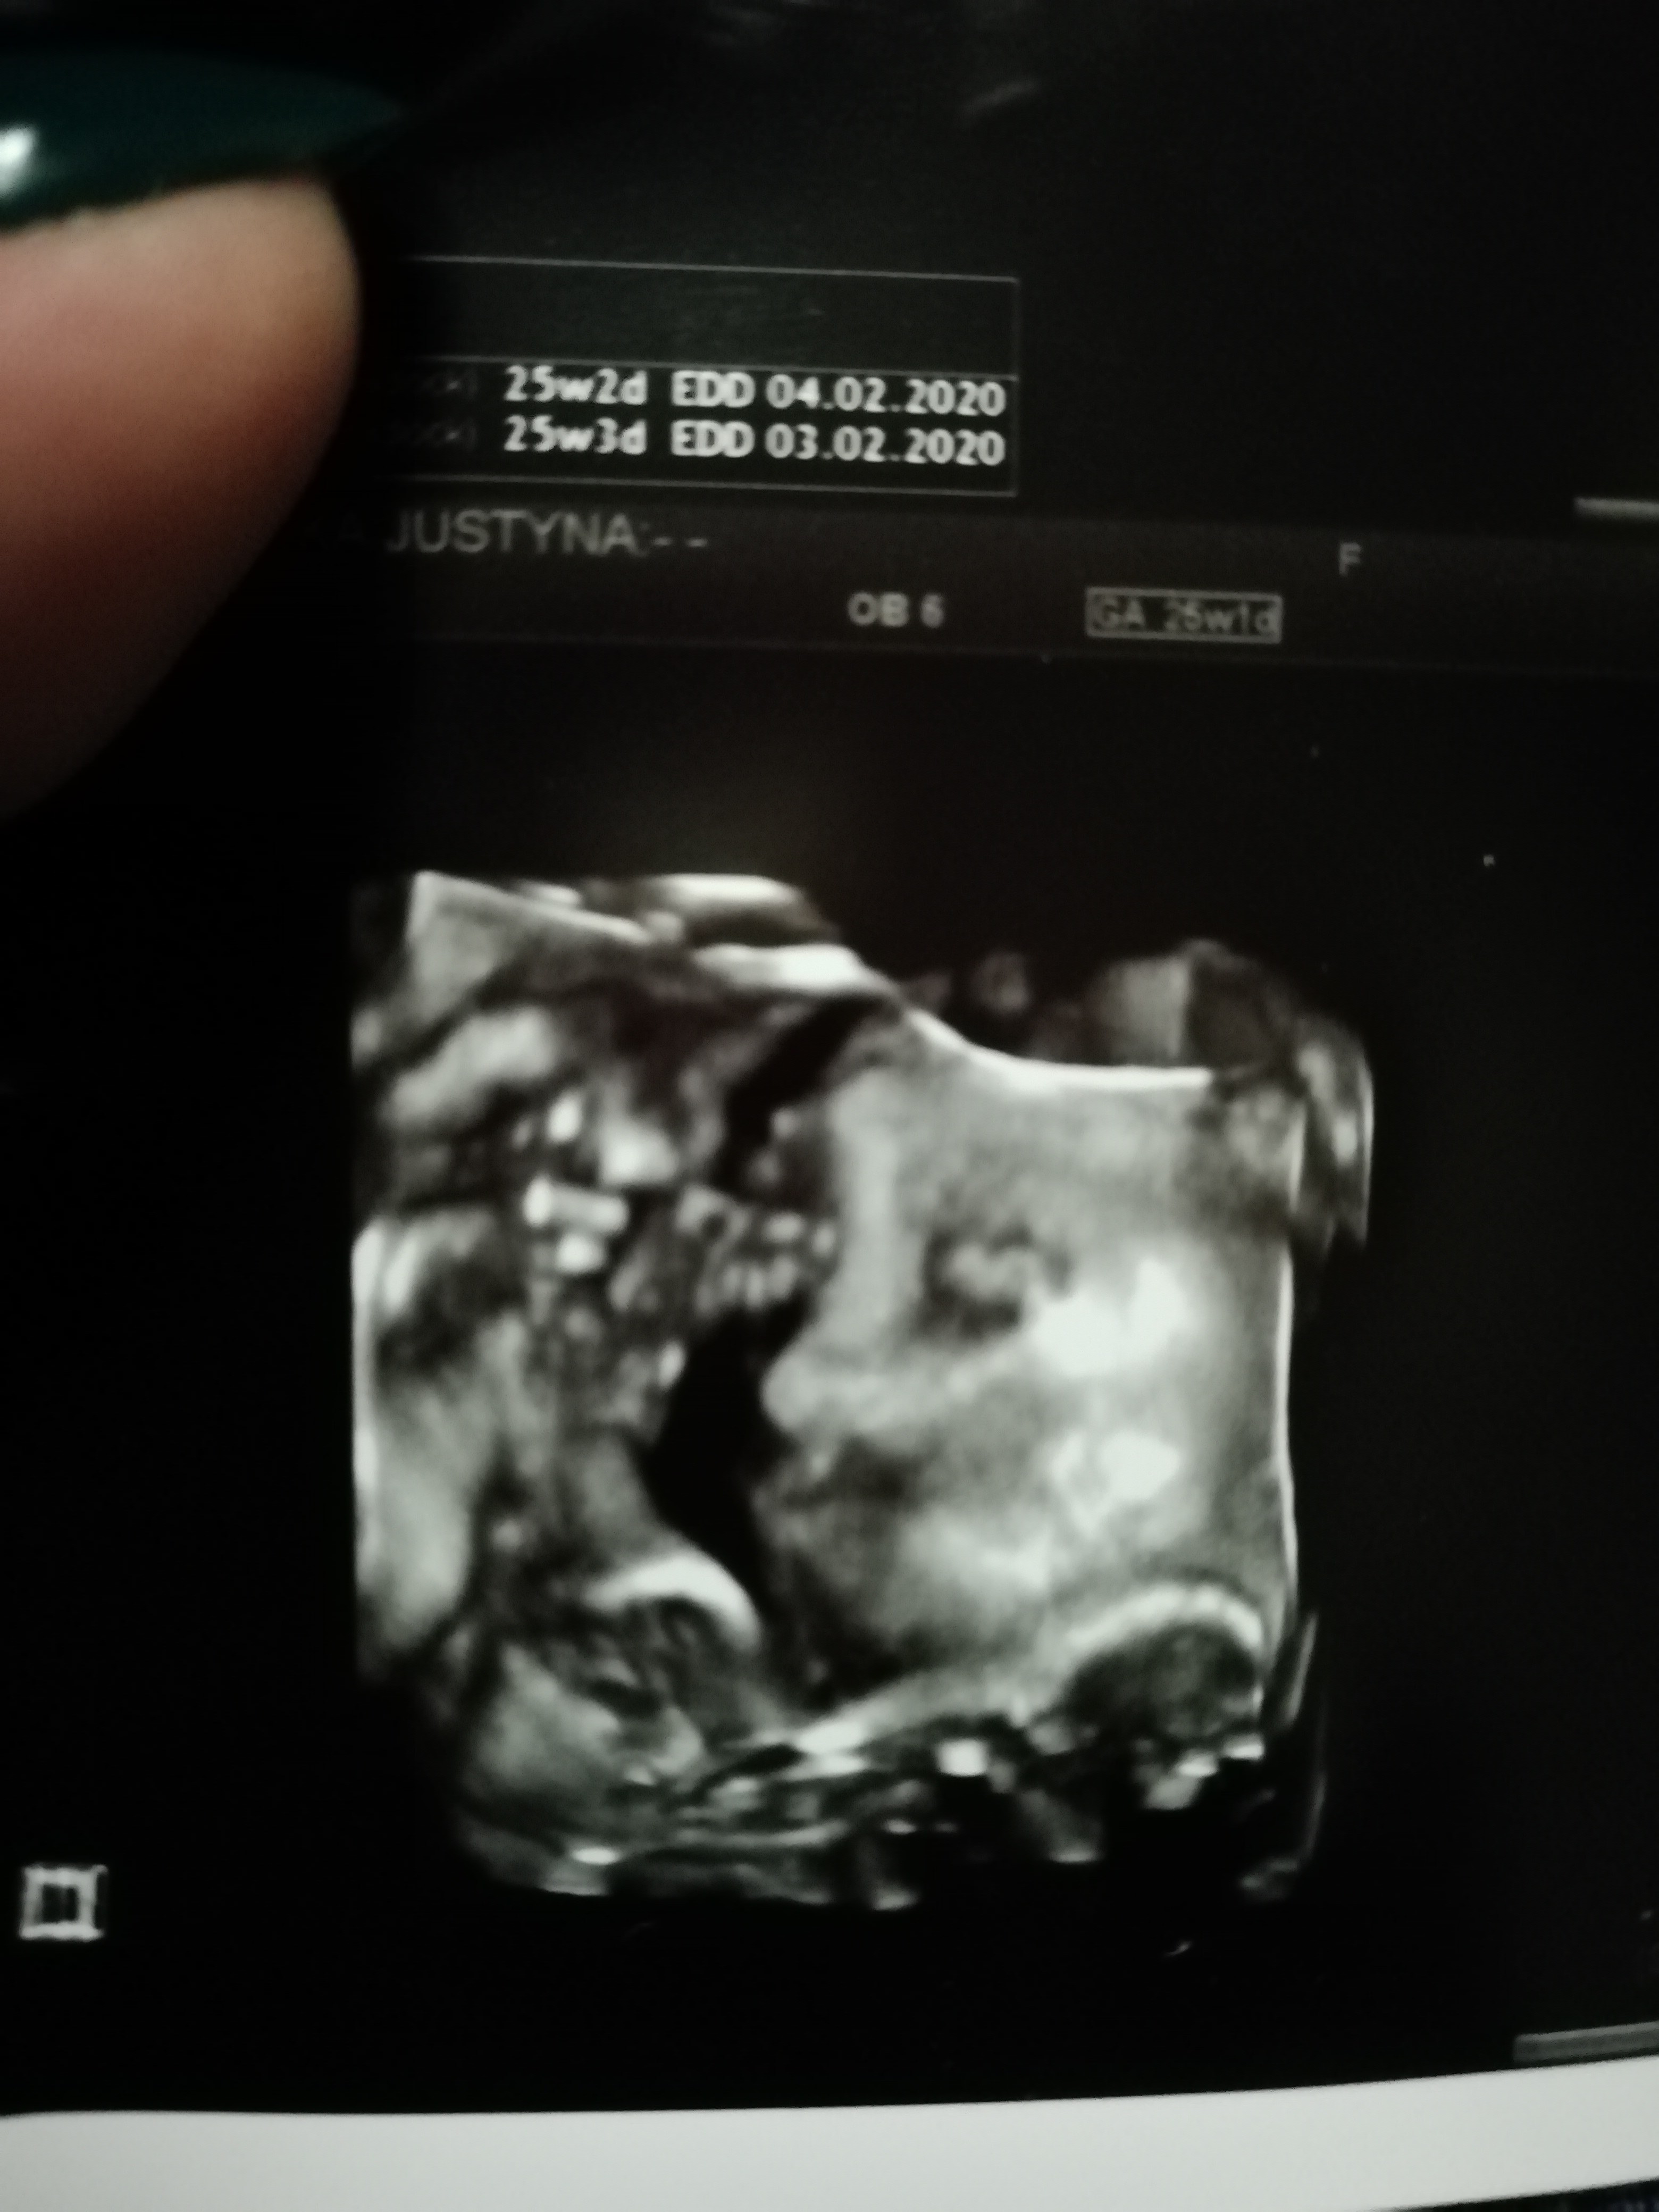

A tu jeszczw nochalek raz :)

IMG_20191024_205527.jpg

Edit : dodam jeszcze ze klusek wazy 809g :P i wg dr jest zzdrowiusienki